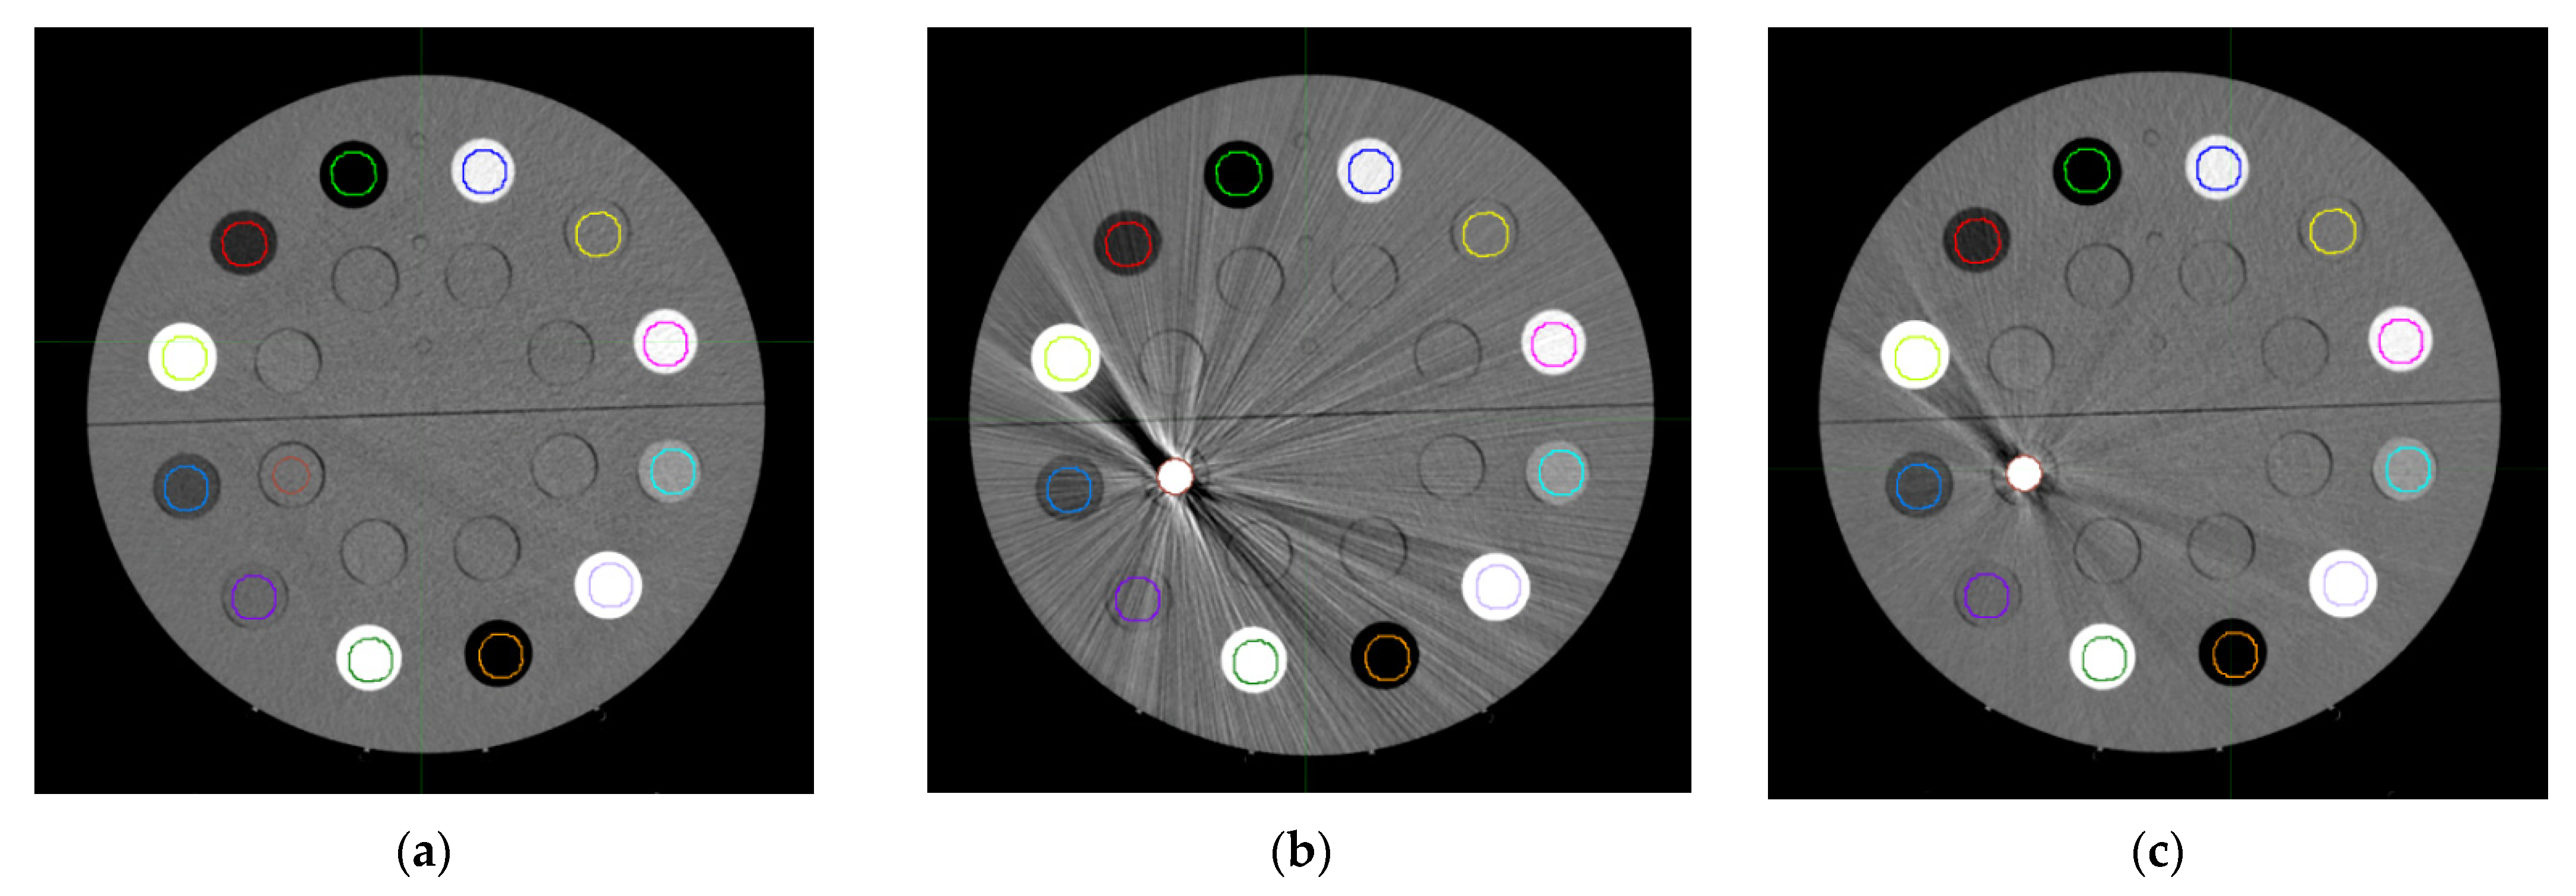

2.3. Metal Artifact Influence on Non-Metal ROIs

3.1. Curve Building and Metal Artifact Influence on Non-Metal ROIs